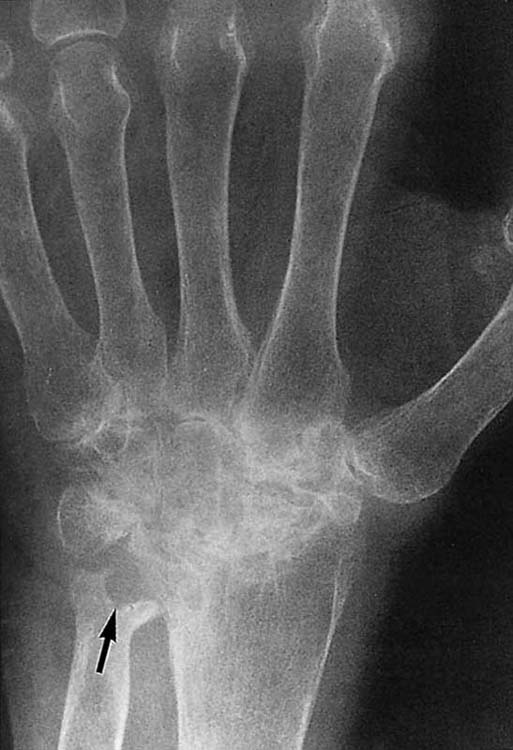

Figure 13-5 Posteroanterior views of the wrist demonstrating the hallmarks of rheumatoid arthritis: osteopenia, which may be the earliest sign of the disease (compare with normal bone density in Fig. 13-1, A), loss of articular cartilage, and erosions. In this patient, erosion is evident at the ulnar styloid (arrow).

images